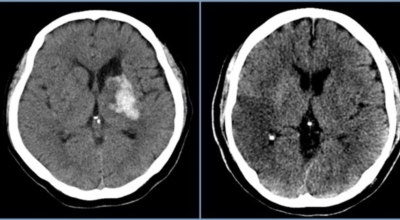

막힌 혈관으로도 혈액이 공급되긴 하나 혈관이 막혀있어 혈액을 보내긴 하나 제대로 흐르지 못하고 혈액이 쌓이고 축적되어 물풍선에 물이 꽉 차서 터지듯 뇌혈관이 터지는 경우가 일어날 수 있는데 이를 뇌출혈 이라고 해요. 물론 외상으로 인한 뇌출혈도 있지만 이처럼 뇌경색으로 인해 혈관이 막혀 터지는 경우도 있어요.

뇌경색 초기증상이 나타나면 가장 중요한 것은 빠른 인지와 빠른 치료예요. 뇌세포는 뇌혈관이 막히는 순간부터 빠르게 손상이 진행이 되고 재생은 어렵기 때문입니다. 뇌와 연관된 질병은 골든타임을 놓치지 않는 것이 제일 중요해요.

큰 뇌혈관이 막힌 경우라면 발생한지 4시간 반 안에 정맥 내로 혈전 용해제를 투여해 막힌 혈관을 뚫어주게 되고 6시간 이내라면 직접 동맥 내 시술을 통해 혈관을 막은 혈전을 직접 제거하는 혈전제거술을 시행하게 되는데요.